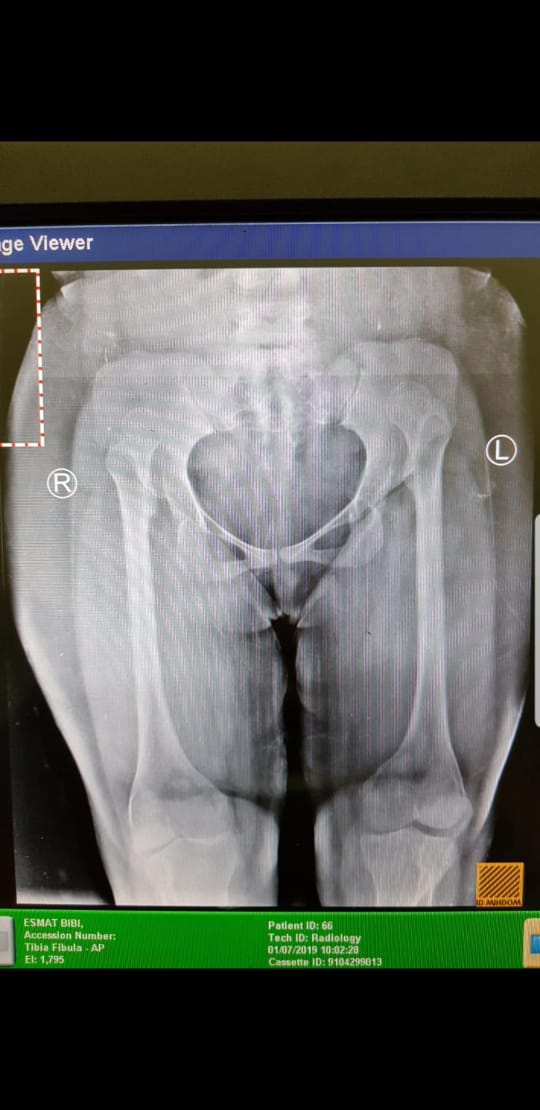

There are some deformities in the bones as seen in the xrays, would want to know about it

Developmental dysplasia of hip bilateral. (DDH). Google it u will know all about it.

there us generalised deformity of all bones and looks shortening as well and Development dysplasia of hip . looks achondroplasic

this is achondroplasia variant of AMC.